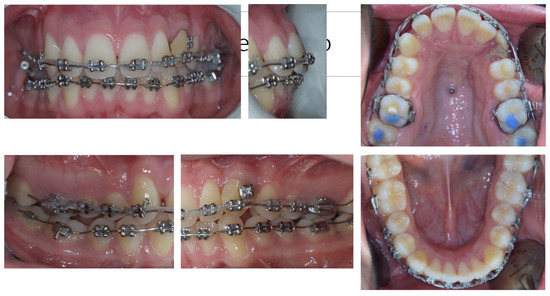

4. Follow-Up and Outcomes